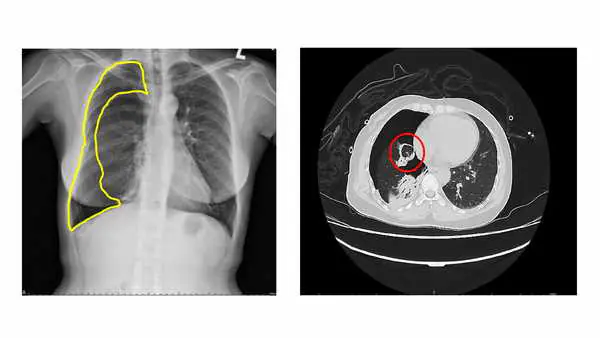

圖二:【左圖】胸部X光顯示右側氣胸(黃線範圍區);【右圖】電腦斷層顯示肺部異常組織(紅圈處)。